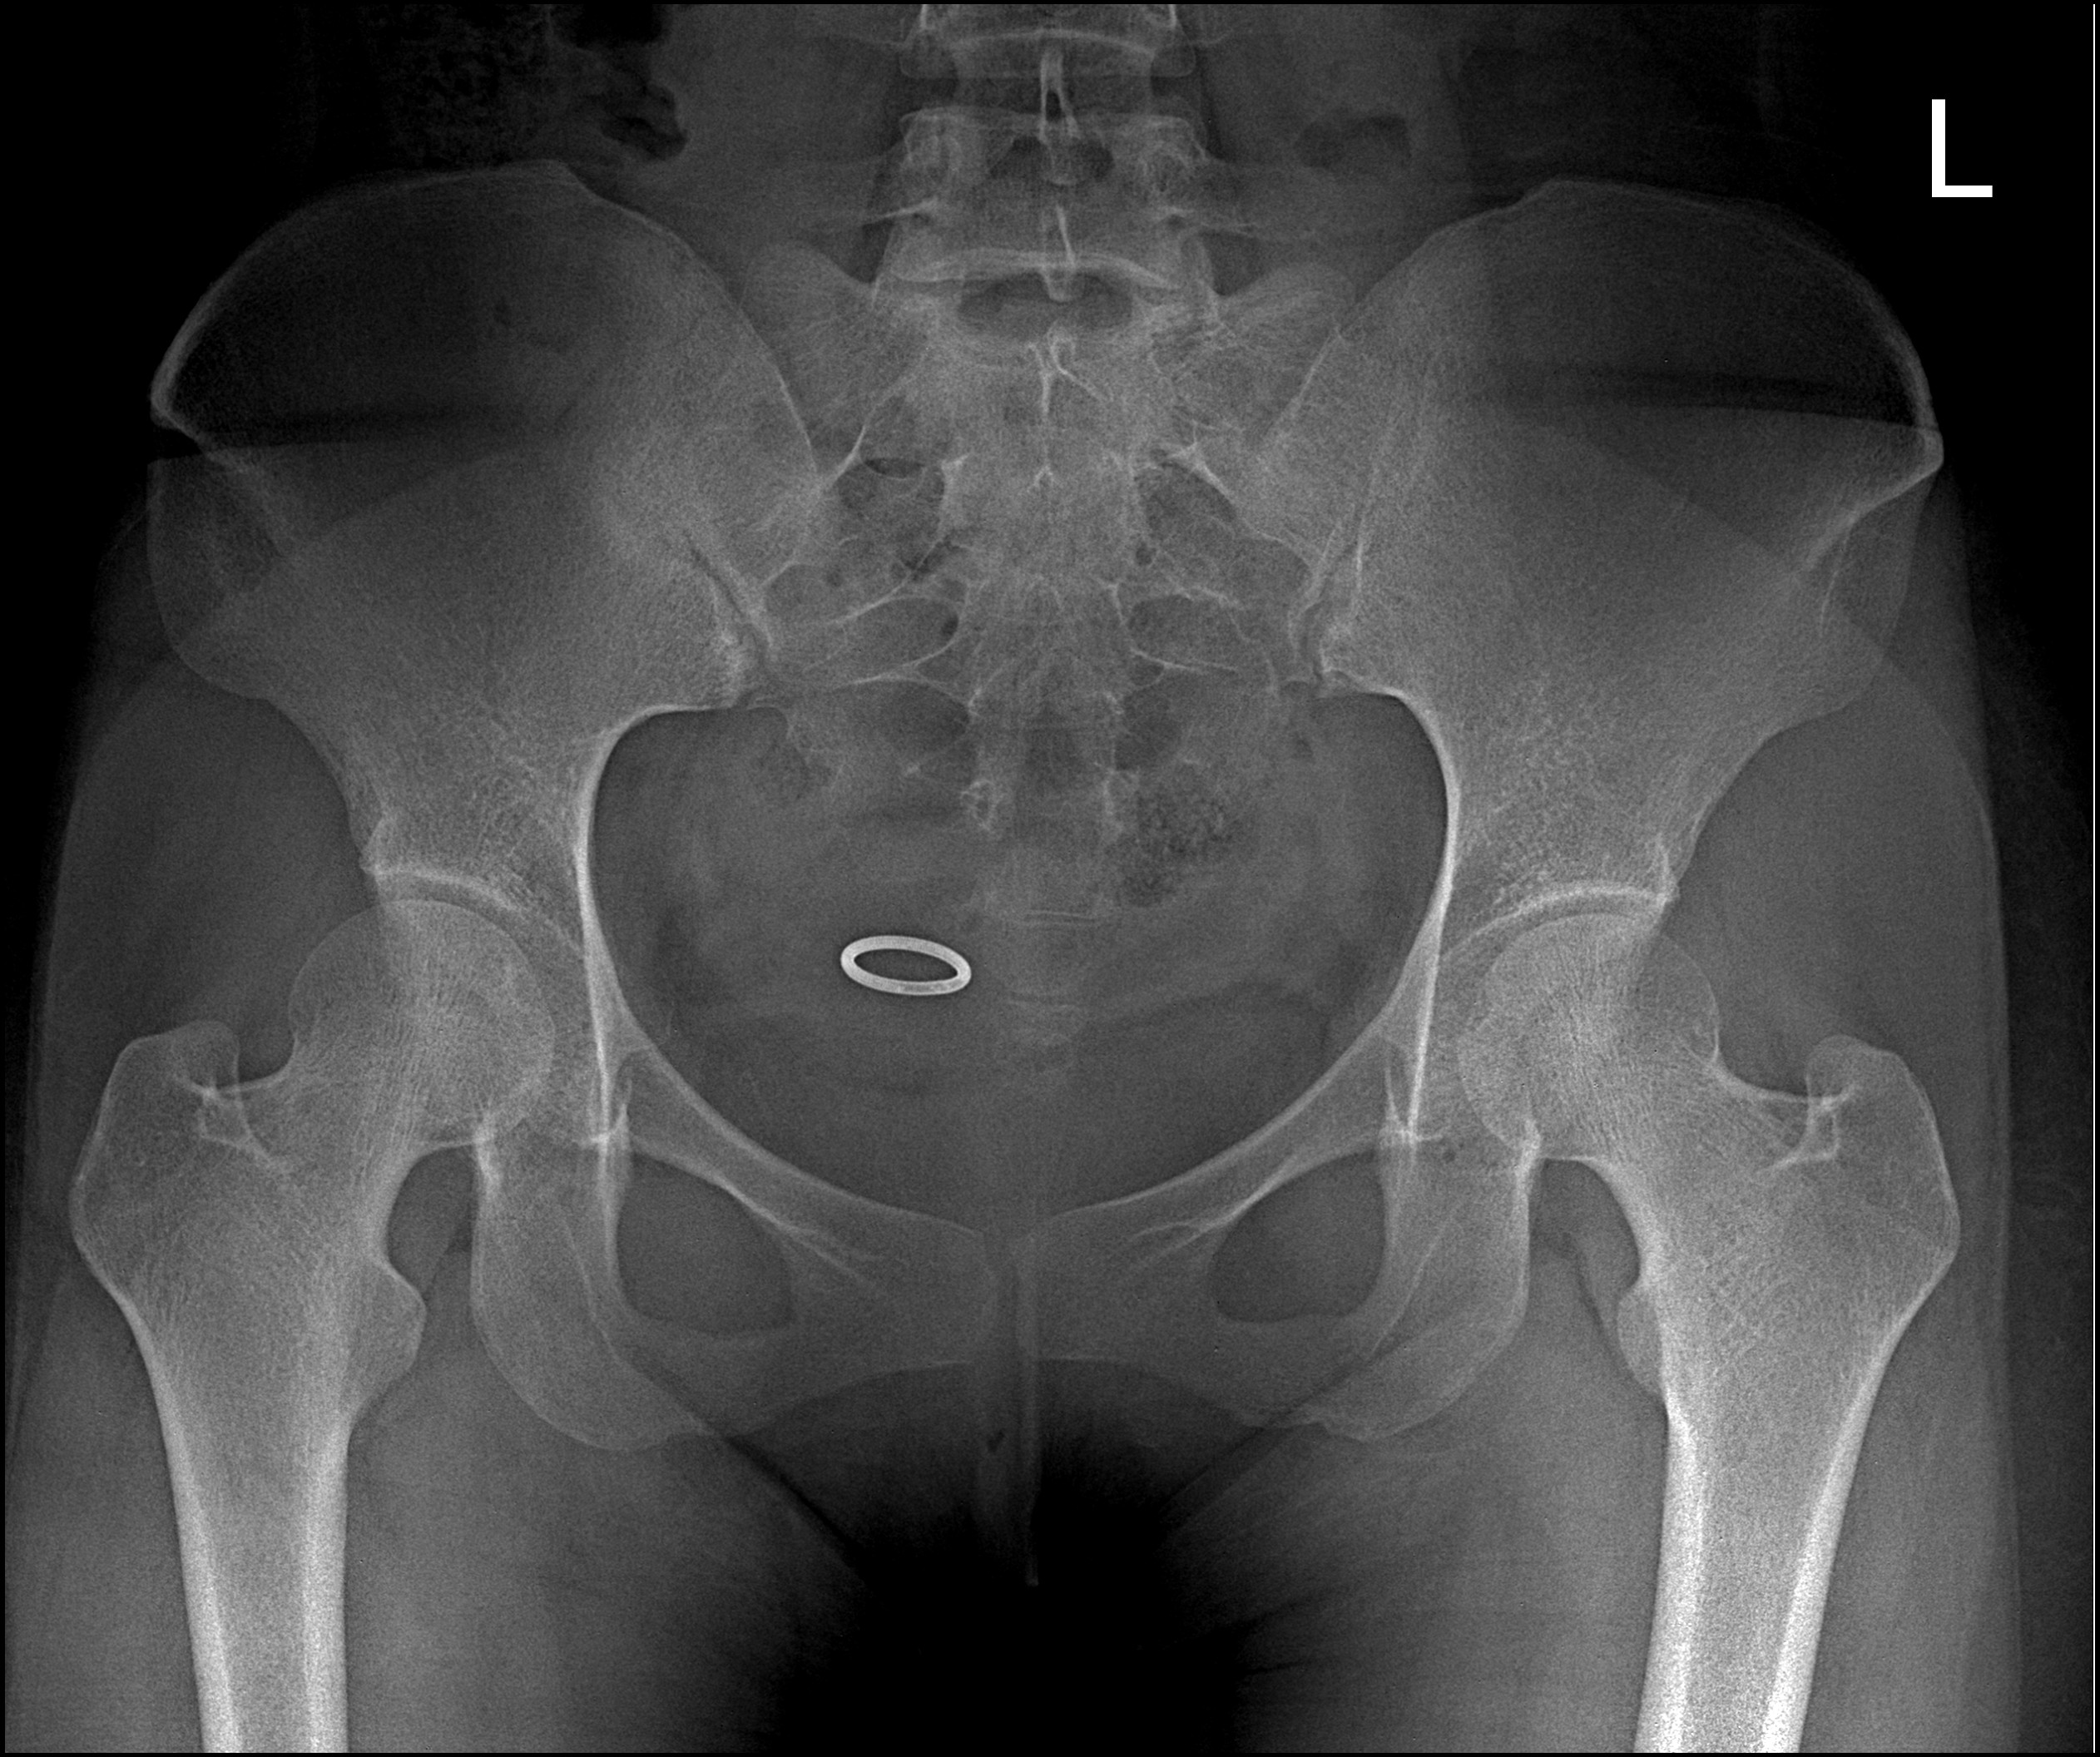

• Clinical Images